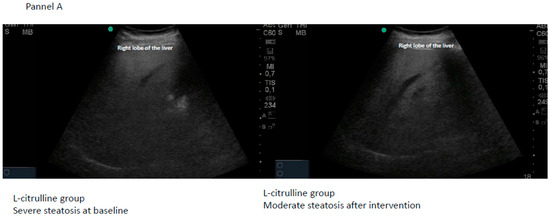

2.7. Steatosis Screening

| Citrulline | Final Steatosis | |||||||

|---|---|---|---|---|---|---|---|---|

| n = 22 | Normal | Mild | Moderate | Severe | Total | Chi-Square | p | |

| Baseline steatosis | Mild | 8 | 2 | 0 | 0 | 10 | 11.589 | 0.0007 |

| Moderate | 1 | 1 | 6 | 0 | 8 | |||

| Severe | 0 | 0 | 2 | 2 | 4 | |||

| Total | 9 | 3 | 8 | 2 | 22 | |||

| Placebo | Final steatosis | |||||||

| n = 20 | Normal | Mild | Moderate | Severe | Total | Chi-square | p | |

| Baseline steatosis | Mild | 3 | 3 | 0 | 0 | 6 | 1.633 | 0.2013 |

| Moderate | 3 | 3 | 6 | 0 | 12 | |||

| Severe | 0 | 0 | 1 | 1 | 2 | |||

| Total | 6 | 6 | 7 | 1 | 20 | |||